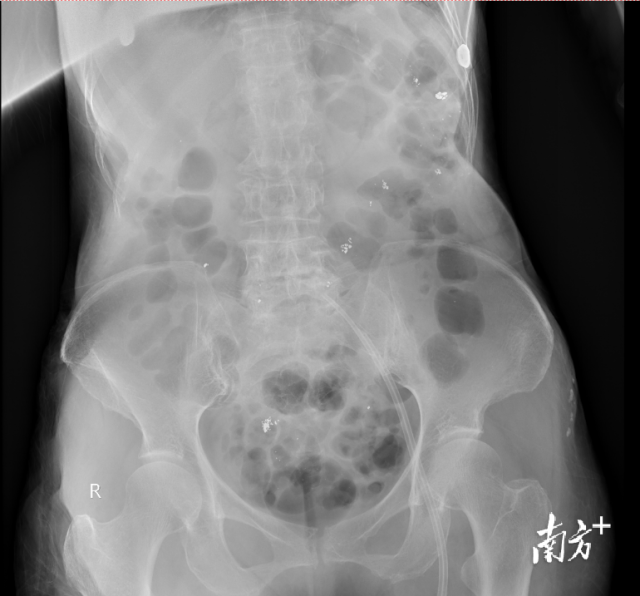

检查可以看到患者消化道内残留大量汞。

入院当天,姜阿婆尿汞浓度高达73465.47μg/L(肌酐校正),比正常值高出一万八千多倍,检查结果反映肾功能的肌酐清除率仅有6.21ml/min,出现无尿,提示已存在肾功能衰竭,转氨酶、心肌酶升高,肝脏、心肌也出现了不同程度的损害。